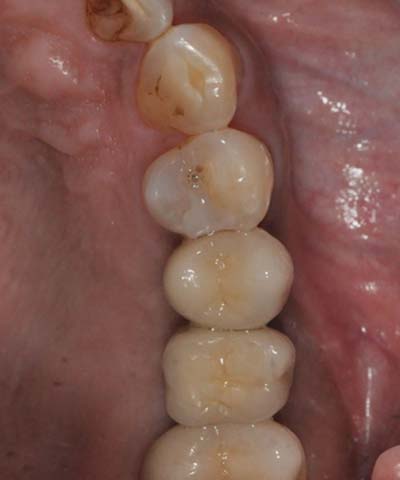

鼻竇增高術(側窗) 首頁 案例分享 人工植牙 鼻竇增高術(側窗) 鼻竇增高術(側窗) 製作多年的牙橋,牙根斷裂,發炎 鼻竇增高術 側面開窗 抬高鼻竇 鼻竇增高術 置入骨粉 覆蓋再生膜,保護骨粉 術後追蹤,傷口良好 裝戴正式假牙 完成 8年追蹤 左上牙根斷裂 植牙重建 九年追蹤